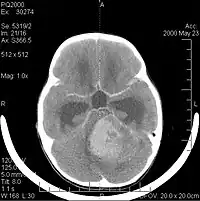

Computertomografi (CT) og magnetisk resonansbilleddannelse (MRI) kan effektivt påvise en neoplasi i hjernen. MR er mere følsom end CT til at identificere læsioner, men har kontraindikationer for patienter med pacemakere, inkompatible proteser, metalclips og andre. CT er fortsat den foretrukne metode til at påvise forkalkninger i læsioner eller knogleerosion af kaloten eller bunden . Brugen af kontrastmidler, som er ioderede i tilfælde af CT og paramagnetiske (gadolinium ) i tilfælde af MR, tillader erhvervelse af information om vaskularisering og integritet af blod-hjerne-barrieren, en bedre definition af den tumorøse tumor sammenlignet til det omgivende ødem og generering af hypoteser om graden af malignitet . Den radiologiske undersøgelse giver også mulighed for en vurdering af de mekaniske virkninger og deraf følgende ændringer i hjernestrukturer som følge af tumoren, såsom hydrocephalus og brok, hvis virkninger kan være dødelige. Til sidst, som forberedelse til operation, kan denne diagnostik bruges til at bestemme placeringen af læsionen eller infiltrationen af tumoren i vitale områder af hjernen. Til dette formål er MR mere effektiv end CT, fordi den kan give tredimensionelle billeder.

Diagnostiske radiologiske billeddannelsesværktøjer fremhæver ændringen i neoplastisk væv sammenlignet med normal hjerneparenkym (gennem ændringer i elektronisk afbildet vævstæthed på CT og signalintensitet på MR). Som de fleste patologiske væv er tumorer også genkendelige ved en øget ophobning af intracellulært vand. I computertomogrammet forekommer de hypodense, dvs. med mindre tæthed end hjerneparenkymet, i det nuklear magnetiske resonans tomogram med spin-gitter-relaksation hypointens og i spin-spin afslapning.

Computertomografi af hjernen viser typisk en vævsmasse, der kan forstærkes af begge kontraster. På CT forekommer lavgradige gliomer sædvanligvis isodense til det normale parenkym og viser derfor muligvis ikke kontrastforstærkning. På samme måde er læsioner i den bagerste kraniale fossa svære at identificere på CT. Følgelig er resultaterne af en sådan tomografi alene ikke altid tilstrækkelige til diagnostiske formål. I tvivlstilfælde er brugen af den mere følsomme magnetiske resonansbilleddannelse afgørende.